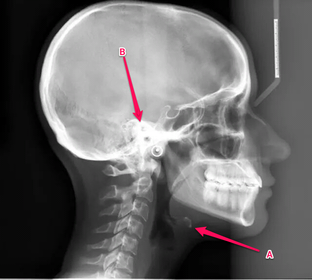

Anatomy practical midyear flashcard revision

anatomy

x-ray